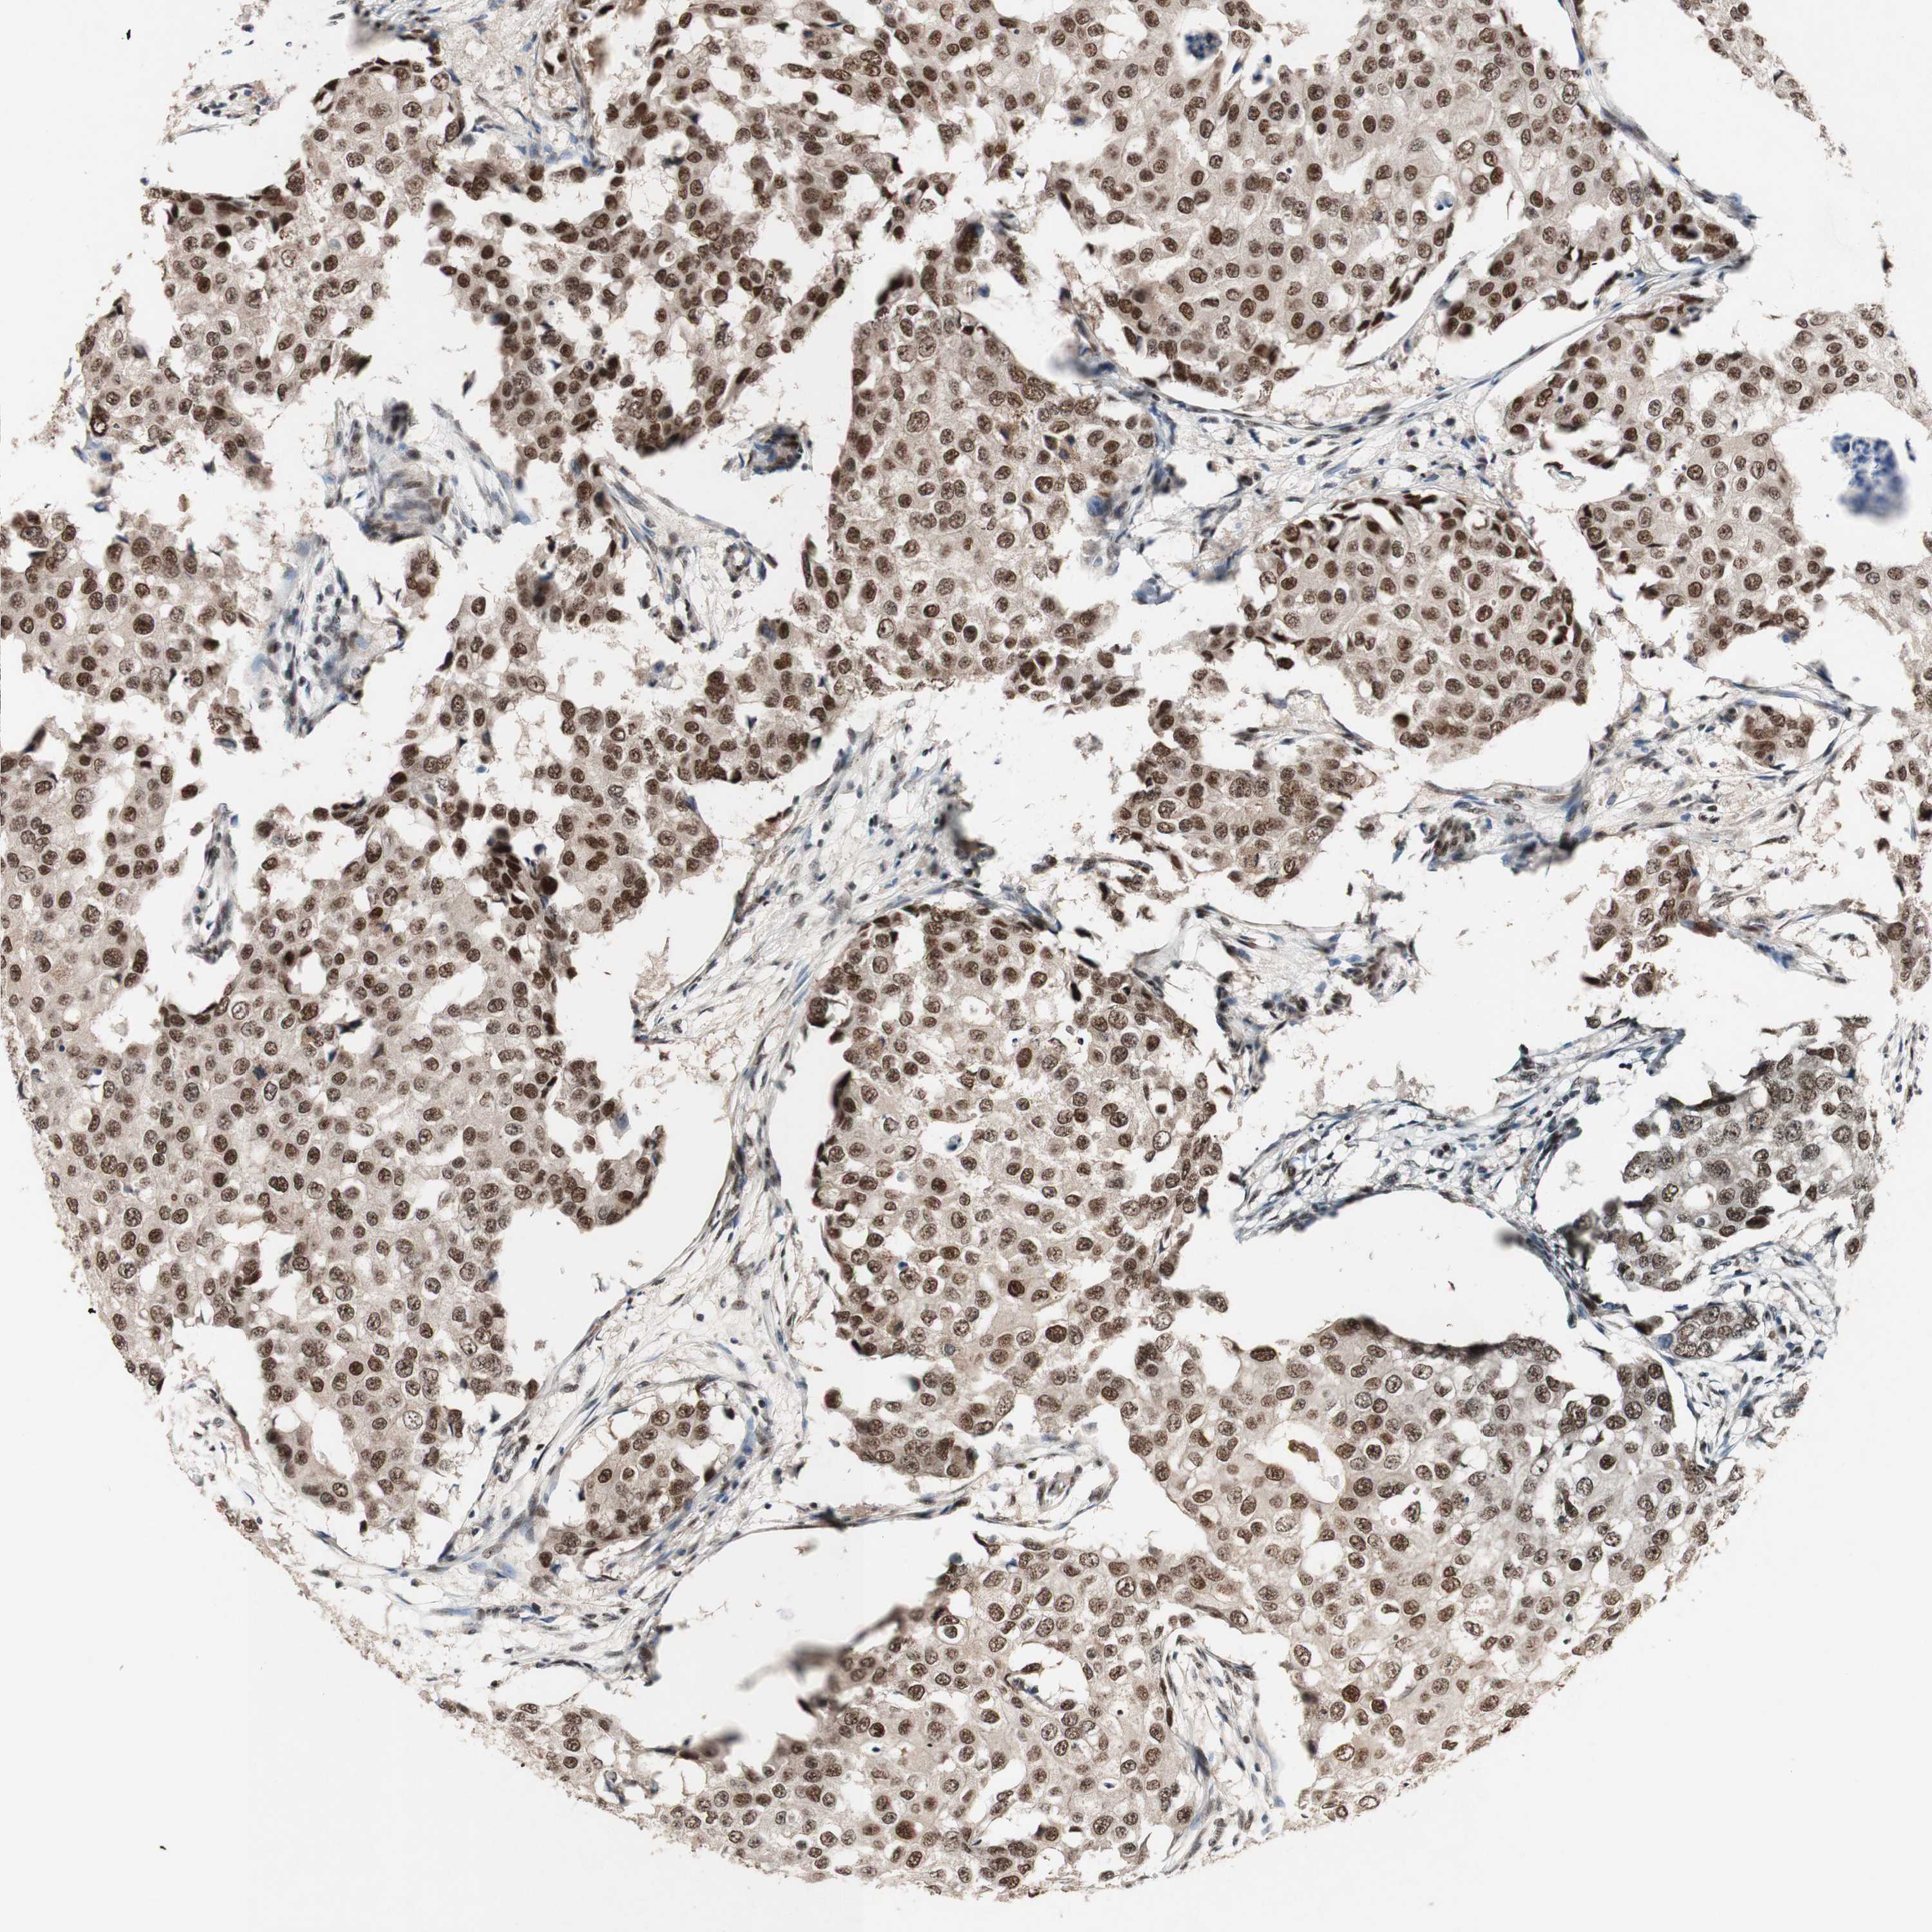

TLE1

CANCER BREAST CANCER Show tissue menu

BRCA TCGA BRCA VALIDATION PROTEIN EXPRESSION